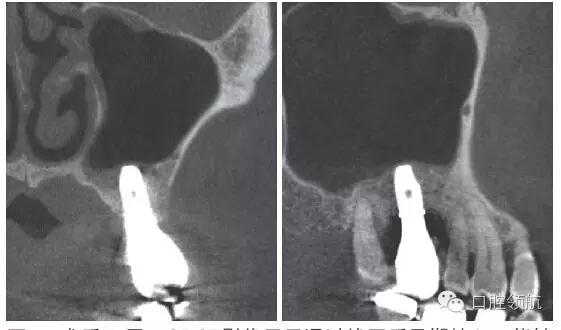

術后12周在獲得骨結合后,開始制作上部結構,術后16周戴入(圖8)。術后24周,CBCT影像顯示,種植體周圍有足夠的骨量(圖9)。

圖9 術后24周,CBCT影像顯示通過拔牙后早期植入,能夠進行安全確實的上頜竇底提升術。